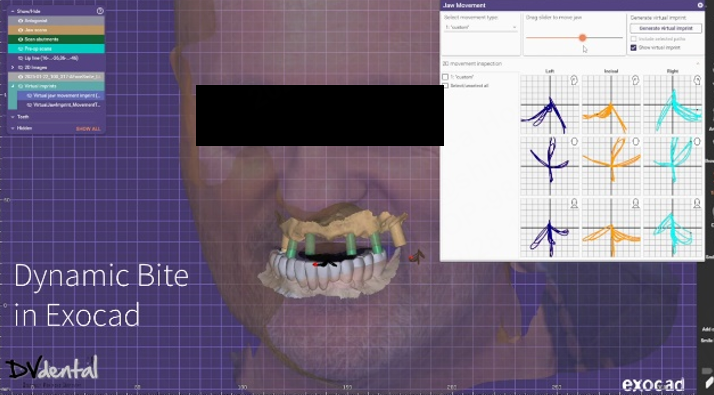

To achieve more precise occlusion, in the final step of the scanning process, Aoralscan Elite can help us capture the dynamic bite, which can be imported into the design software for subsequent dynamic occlusal design.

3. Design in exocad

After the capture process is done, we send everything to the lab. The lab mounts the data on the virtual articulator with the help of the face-scan, and designs a facially driven prosthesis for the upper jaw according to the patient’s needs. The integration of the dynamic bite within the CAD software allowed us to finalize our design functionally.